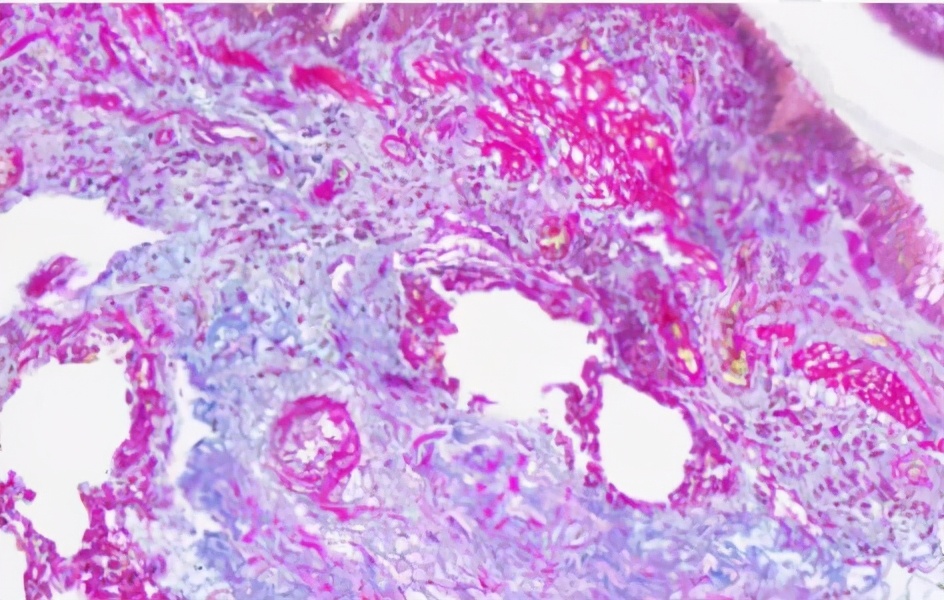

Masson染色(马松三色)

用途:用于胶原纤维和肌纤维的鉴别染色。

结果判读:胶原纤维、粘液、软骨呈蓝色,肌纤维、纤维素和红细胞染红色,细胞核染蓝黑色。